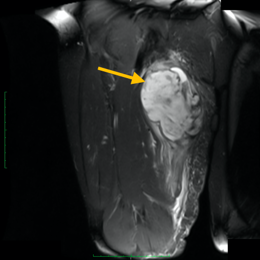

Radiographic imaging is used to help form a diagnosis of CCs. These include X-Ray, MRI, CT and Bone Scans

An example of an CC MRI is shown.